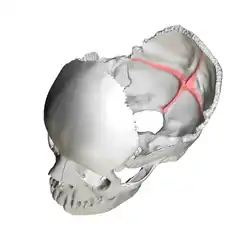

Human skull. Position of cruciform eminence is shown in red. | |

The cruciform eminence (or cruciate eminence) divides the deeply concave internal surface of the occipital bone into four fossae:

The upper fossae are separated from the lower fossae by a groove for the transverse sinuses. At the point of intersection between all four fossae is the internal occipital protuberance.